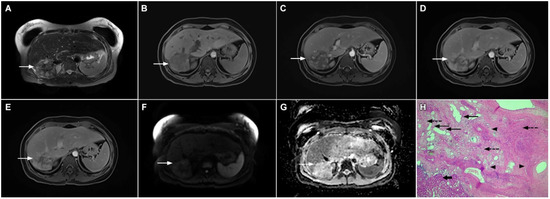

Mucinous cholangiocarcinoma is a rare variant of mICC characterized by rich mucin production [24,27]. According to previous studies, mucinous mICC originate from mucin-producing cholangiocytes located in large bile ducts [28]. Imaging findings in mucinous mICC reflect characteristic histopathological features of the lesion with cancer cell nests suspended in a large mucinous lake [29]. Therefore, these lesions display strong T2-weighted hyperintensity [27]. Moreover, as cancer cells in the center of the lesion are scarce, these tumors show only slight progressive enhancement of intralesional septa and cellular nests in postcontrast studies (Figure 7) [27]. Due to its very high signal intensity on T2-weighted images and centripetal pattern of enhancement, mucinous mICC may be misdiagnosed as hemangiomas [29]. Concerning similarities in the postcontrast behavior of mucinous mICC and hemangiomas, it should be kept in mind that mICC displays continuous ragged rim enhancements in contrast to the discontinuous, stronger peripheral and centripetal enhancement following the blood pool seen in hemangiomas [24,29].

Figure 7.

Mucin-rich mass-forming cholangiocarcinoma in a 78-year-old woman. The axial T2-weighted image (A) shows the lobulated hyperintense lesion (arrow) located in the subcapsular region of liver segment IVB, which is associated with capsular retraction. On the plain T1-weighted image (B) the lesion (arrow) is hypointense. In the arterial phase (C), ring enhancement can be seen with slight “ragged” central enhancement in the portal venous (D) and delayed phase (E). On DWI, diffusion restriction is noted on the periphery of the lesion (arrow) while no restriction is seen in the central part of the tumor (F). Corresponding ADC map showing targetoid appearance of the lesion is shown on (G). Hematoxylin and eosin (H&E) staining (H) showed cholangiocarcinoma (arrows) adjacent to normal liver parenchyma (dashed arrow); original magnification ×40.